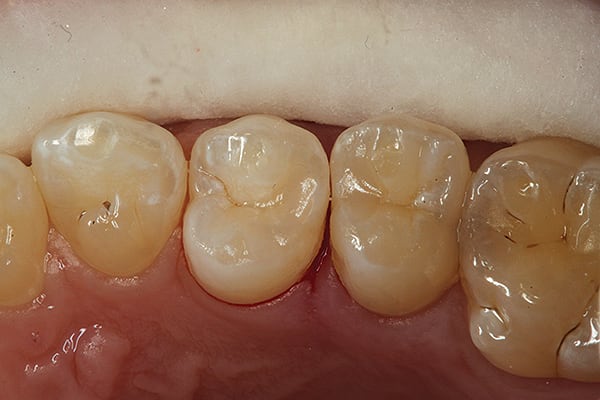

8. The final tunnel preparations and restorations completed. This procedure proved to be a “win–win” for doctor and patient—the patient wins because of the conservative and highly esthetic nature of the procedure, and the dentist wins because it is a stress-free Class II restoration.